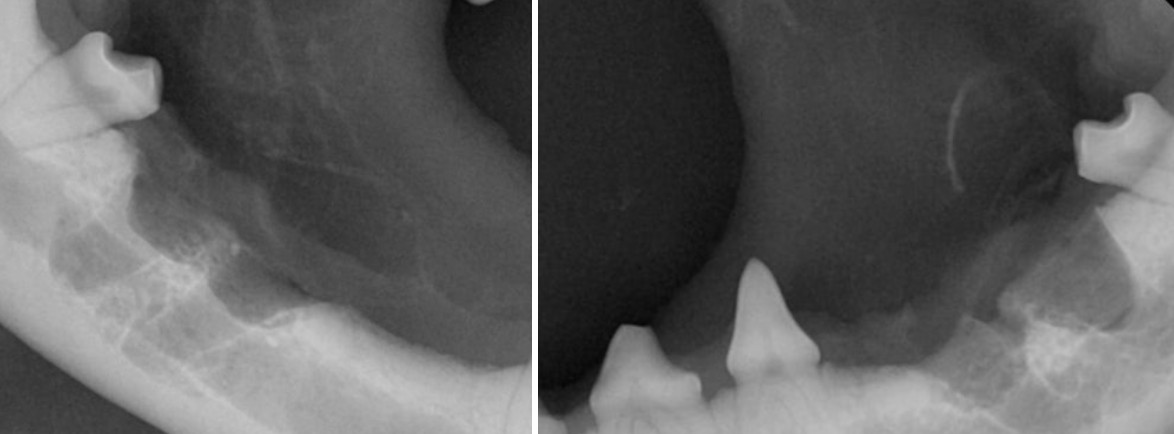

그러나 방사선 촬영을 해보면 치수관이 정상적으로 이어지지 않고 끊긴 음영 이중 구조처럼 보이는 치근 내부 형태 세균 침투 통로가 형성된 공간 이 확인됩니다.

방사선 촬영 결과

양측 상악 제1대구치(M1)에서 치내치 전형적 소견이 확인되었습니다.

이미 치조골 소실이 동반되어 있었고 치아 기능 유지가 어려운 상태였습니다.